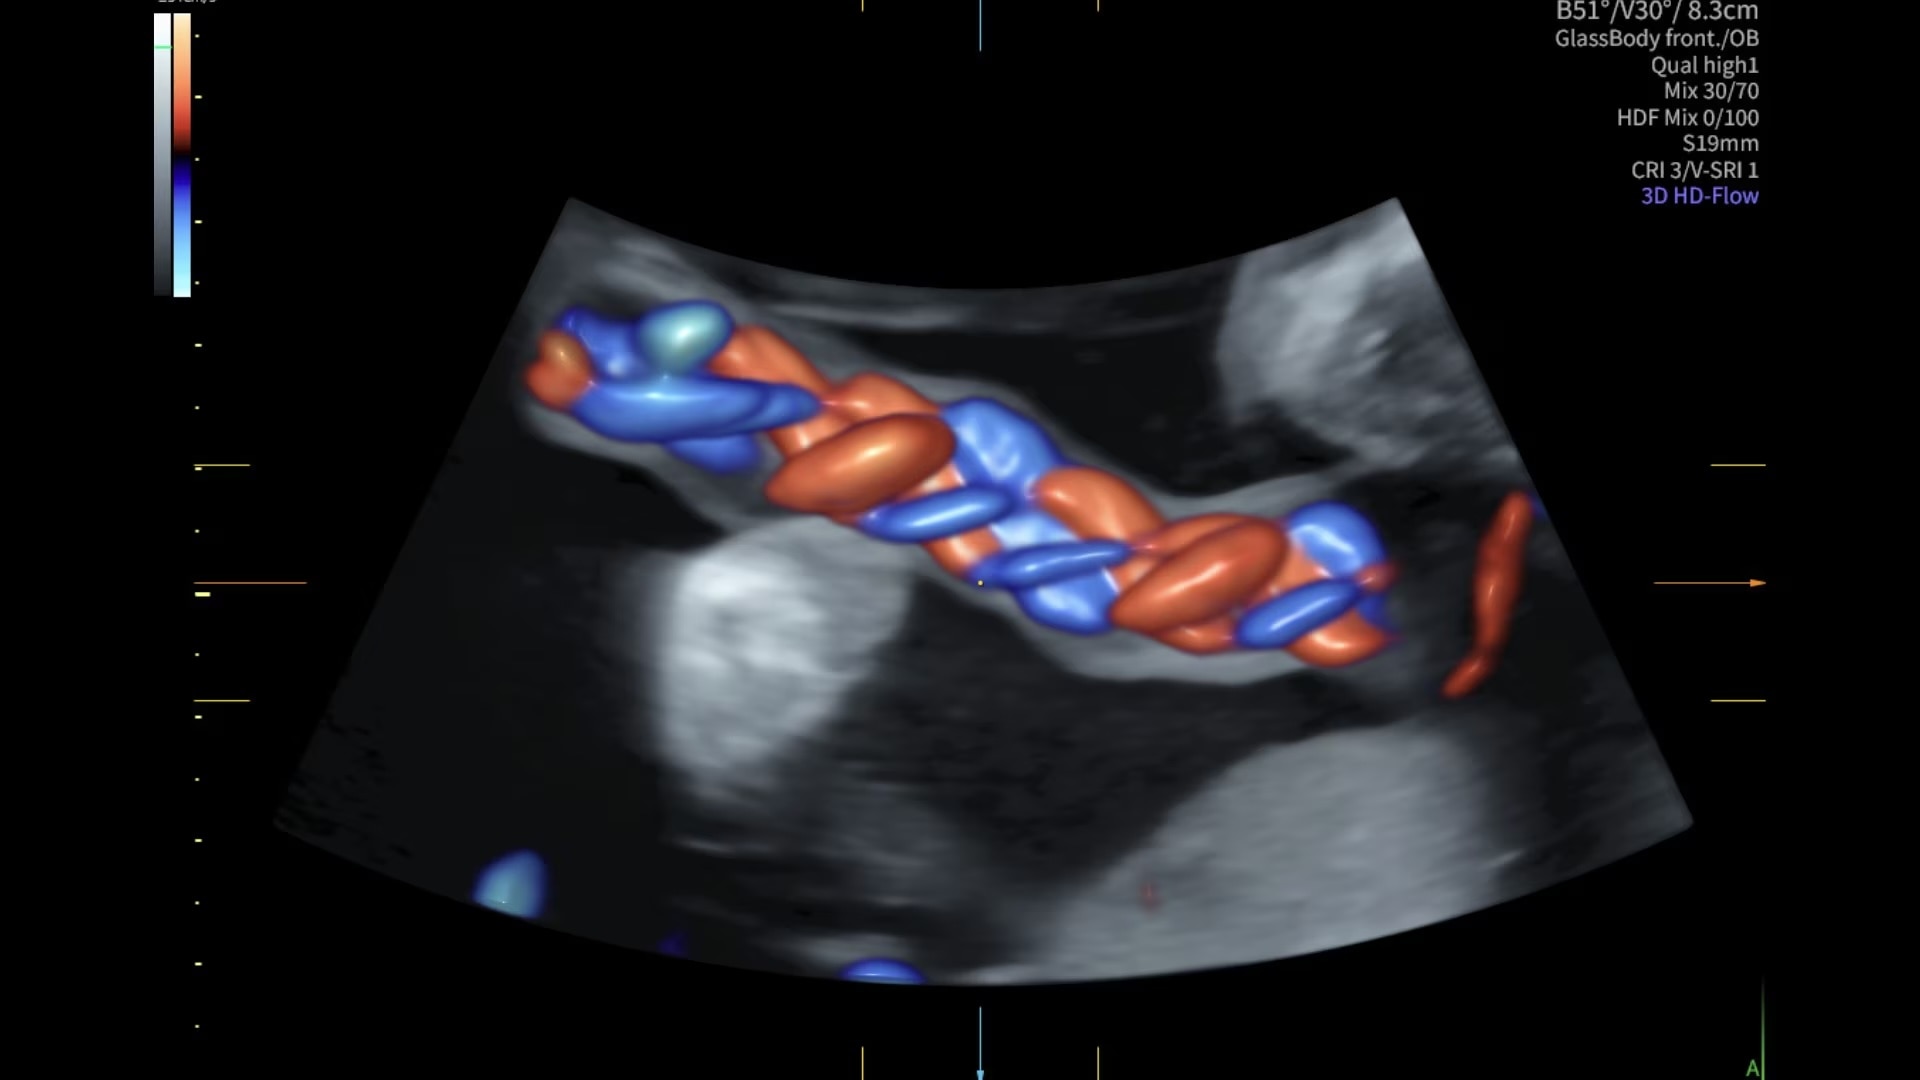

Next level color Doppler for easy, fast visualization of blood flow, displaying a 3D-like appearance.

Uses Color Doppler amplitude to create a 3D-like appearance, helping to clearly separate blood vessels with less flash artifact, improving vessel edge clarity. Available in all color modes, Radiantflow can also be combined with other imaging techniques like spectral Doppler and color M-mode, making it especially useful for visualizing major vessels such as the 3-vessel view (3VV), umbilical cord, arotic arch, and more.